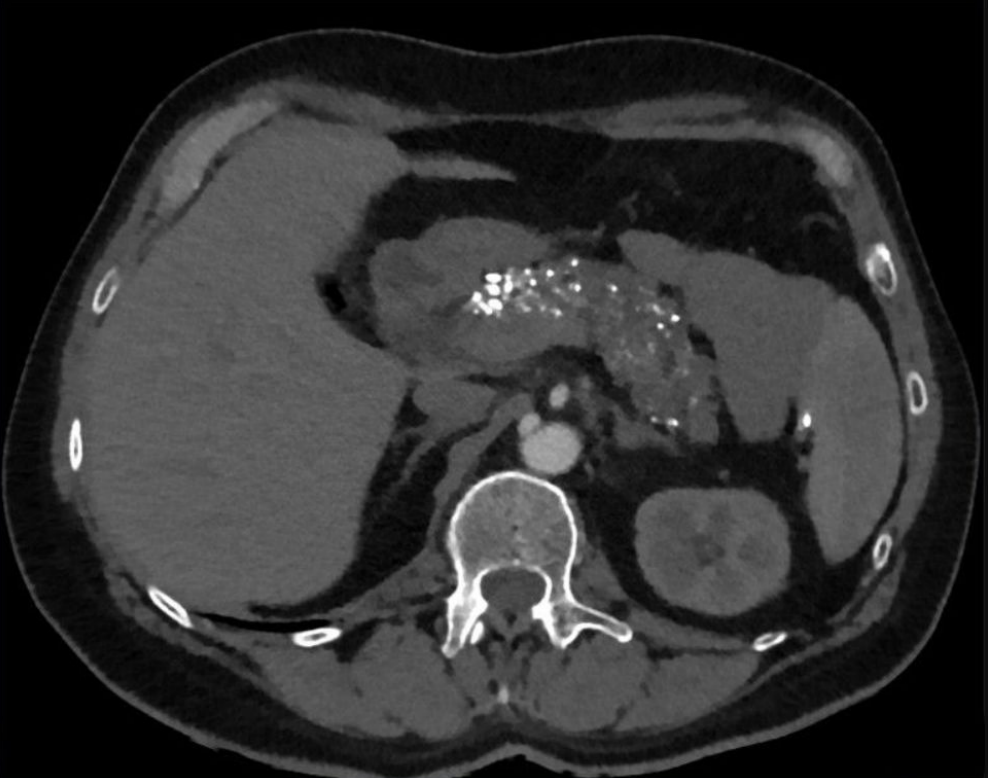

What do you expect to see on imaging for chronic pancreatitis?

A

• Calcification of pancreas

• Change in size (atrophy or enlargement)

• Fibrosis (hyperechoic)

• Pseudoaneurysms, pseudocyts

• Dilation of pancreatic duct

Diagnosis of acute pancreatitis requires 2/3 features: 1. Acute onset severe epigastric pain 2. Elevated amylase/lipase 3. CT imaging (or MRI)

Diagnosis of acute pancreatitis requires 2/3 features: 1. **Acute onset severe epigastric pain** 2. **Elevated amylase/lipase** 3. **CT imaging (or MRI)**